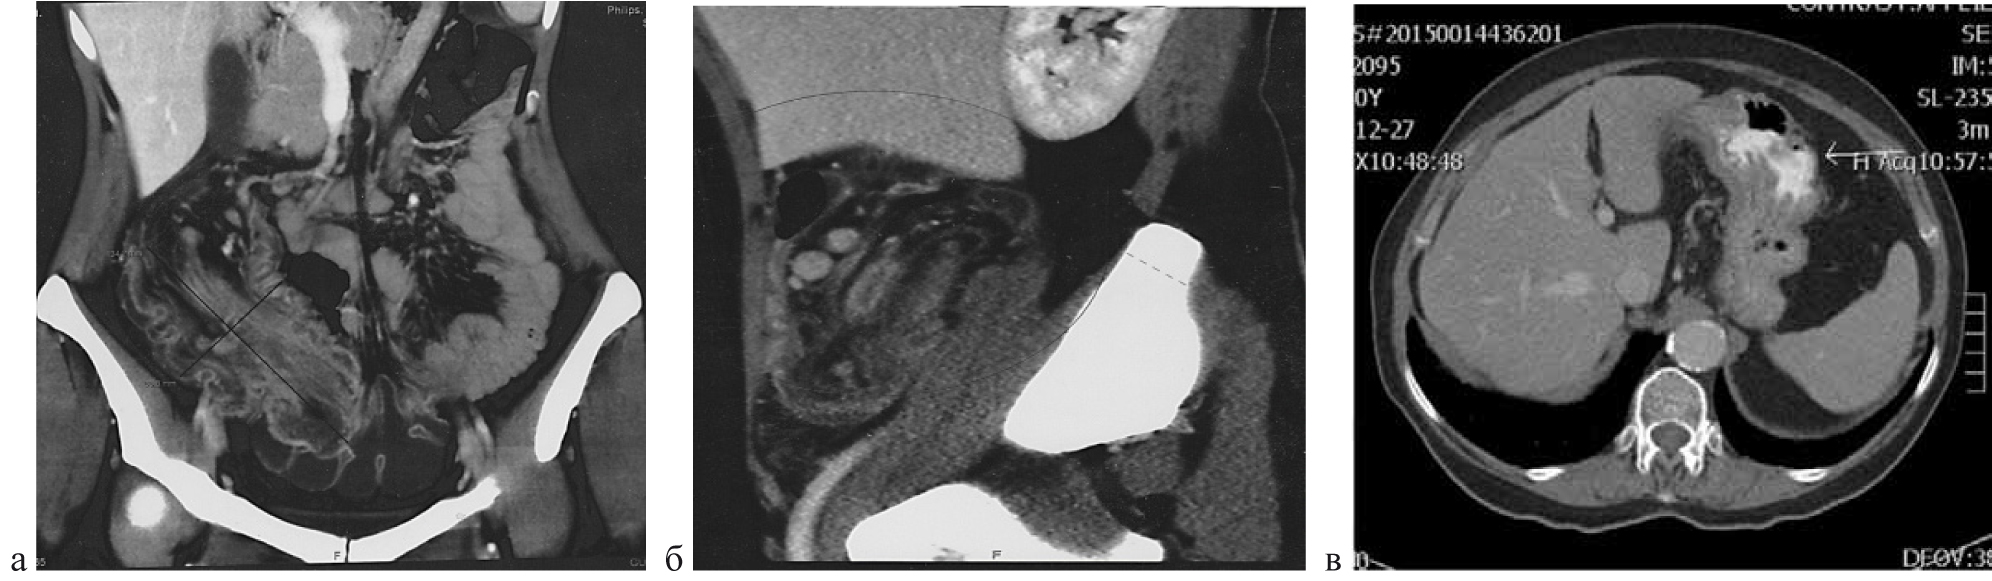

Наиболее информативным методом обследования при ООТК мы считаем МСКТ брюшной полости в режиме ангиографии, которая у 31 пациента (59,6 %) позволила не только диагностировать, но и стадировать ООТК, выявить характерные признаки, соответствующие гистологической структуре опухоли. Выявлены общие патогномоничные признаки ООТК: при эндофитном росте опухоли локальные изменения проявлялись утолщением стенки кишки более 10–15 мм и сужением ее просвета, экзофитный тип проявляется узлом, растущим в просвет кишки. При контрастном усилении ткань опухоли накапливала контрастный препарат более интенсивно, чем подслизистый и мышечный слои неизмененной стенки кишки. Лимфомы на компьютерных томограммах проявлялись либо узловой инфильтрацией, либо утолщением стенки кишки в пределах сегмента, при этом накопление препарата происходило преимущественно по периферии опухоли в виде тонкого ободка, что отражало окрашивание неизменной слизистой оболочки. Саркомы представляли неоднородные по структуре образования с признаками инфильтративного роста. Неоднородность была обусловлена, как правило, массивным некрозом и последующим развитием кистозной дегенерации. Для сарком, при контрастном усилении, было характерно интенсивное, неоднородное окрашивание опухоли и значительная инфильтрация окружающей кишку жировой клетчатки. Гастроинтестинальные стромальные опухоли (GIST) на МСКТ имели вид ограниченного мягкотканого экзофитного образования, с признаками экспансивного роста. Доброкачественные GIST имели однородную структуру, при контрастном усилении интенсивно окрашивались, что часто служило их «визитной карточкой». Злокачественные GIST при контрастном усилении чаще проявлялись неоднородной структурой, что объясняется развитием в структуре опухоли некротических изменений и кистозной дегенерации (рис. 5).

Рис. 5. МСКТ брюшной полости в режиме ангиографии: а) эндофитная опухоль в инвагинате; б) лимфома подвздошной кишки; в) аденокарцинома двенадцатиперстной кишки